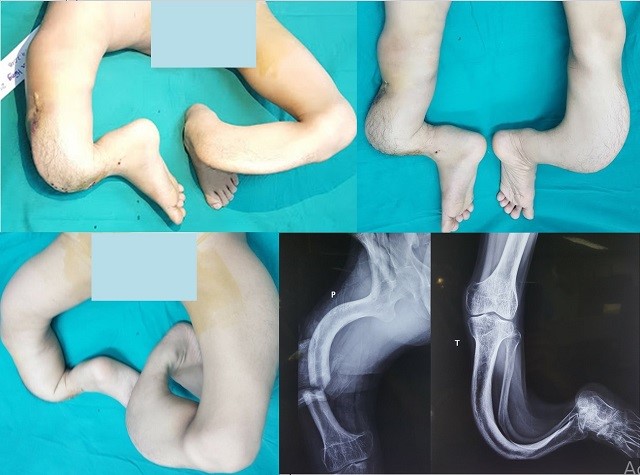

Hai chân cong như rễ cây của bệnh nhân

GS, TSKH, TTND Nguyễn Thế Hoàng, Phó Giám đốc Hubet com cá cược thể thao Trung ương Quân đội 108 chia sẻ, khi nhìn thấy đôi chân của Hùng, các bác sĩ chuyên ngành đều rất kinh ngạc vì một dị dạng phức tạp đến kỳ lạ và khó tin mà suốt cả hơn 30 năm làm nghề, họ chưa bao giờ nhìn thấy.

Mà trong đó, những tổn thương kỳ lạ của H là chiều dài xương hai bên khác biệt, toàn bộ hệ thống xương khớp ở vùng đùi, cẳng chân và bàn chân đều bị biến dạng cong vẹo và phức tạp theo nhiều chiều, nhiều hướng khác nhau, xương bị thưa loãng nặng... Thách thức đặt ra, nếu không chữa khỏi, sẽ phải cắt bỏ cả hai chi.